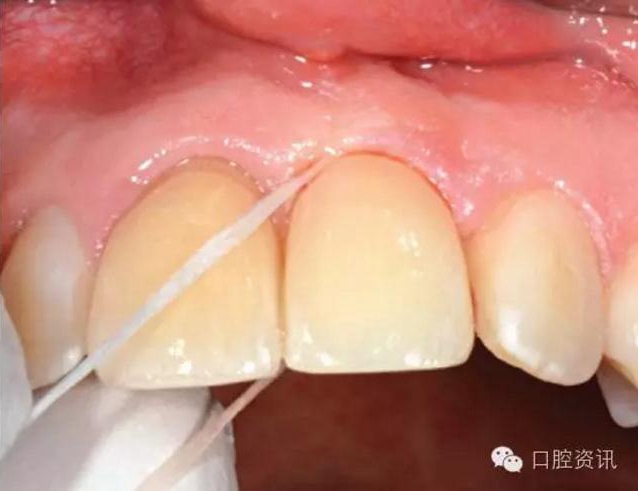

我們也希望您可以保質(zhì)保量地進(jìn)行口腔清潔,每日兩次刷牙、漱口以

及使用牙線、間隙刷等,都是最基本的要求。由于種植牙的構(gòu)造與天

然牙不同,有時您也需要一些特定的清潔工具。

15.jpg

圖15. 使用牙線清潔